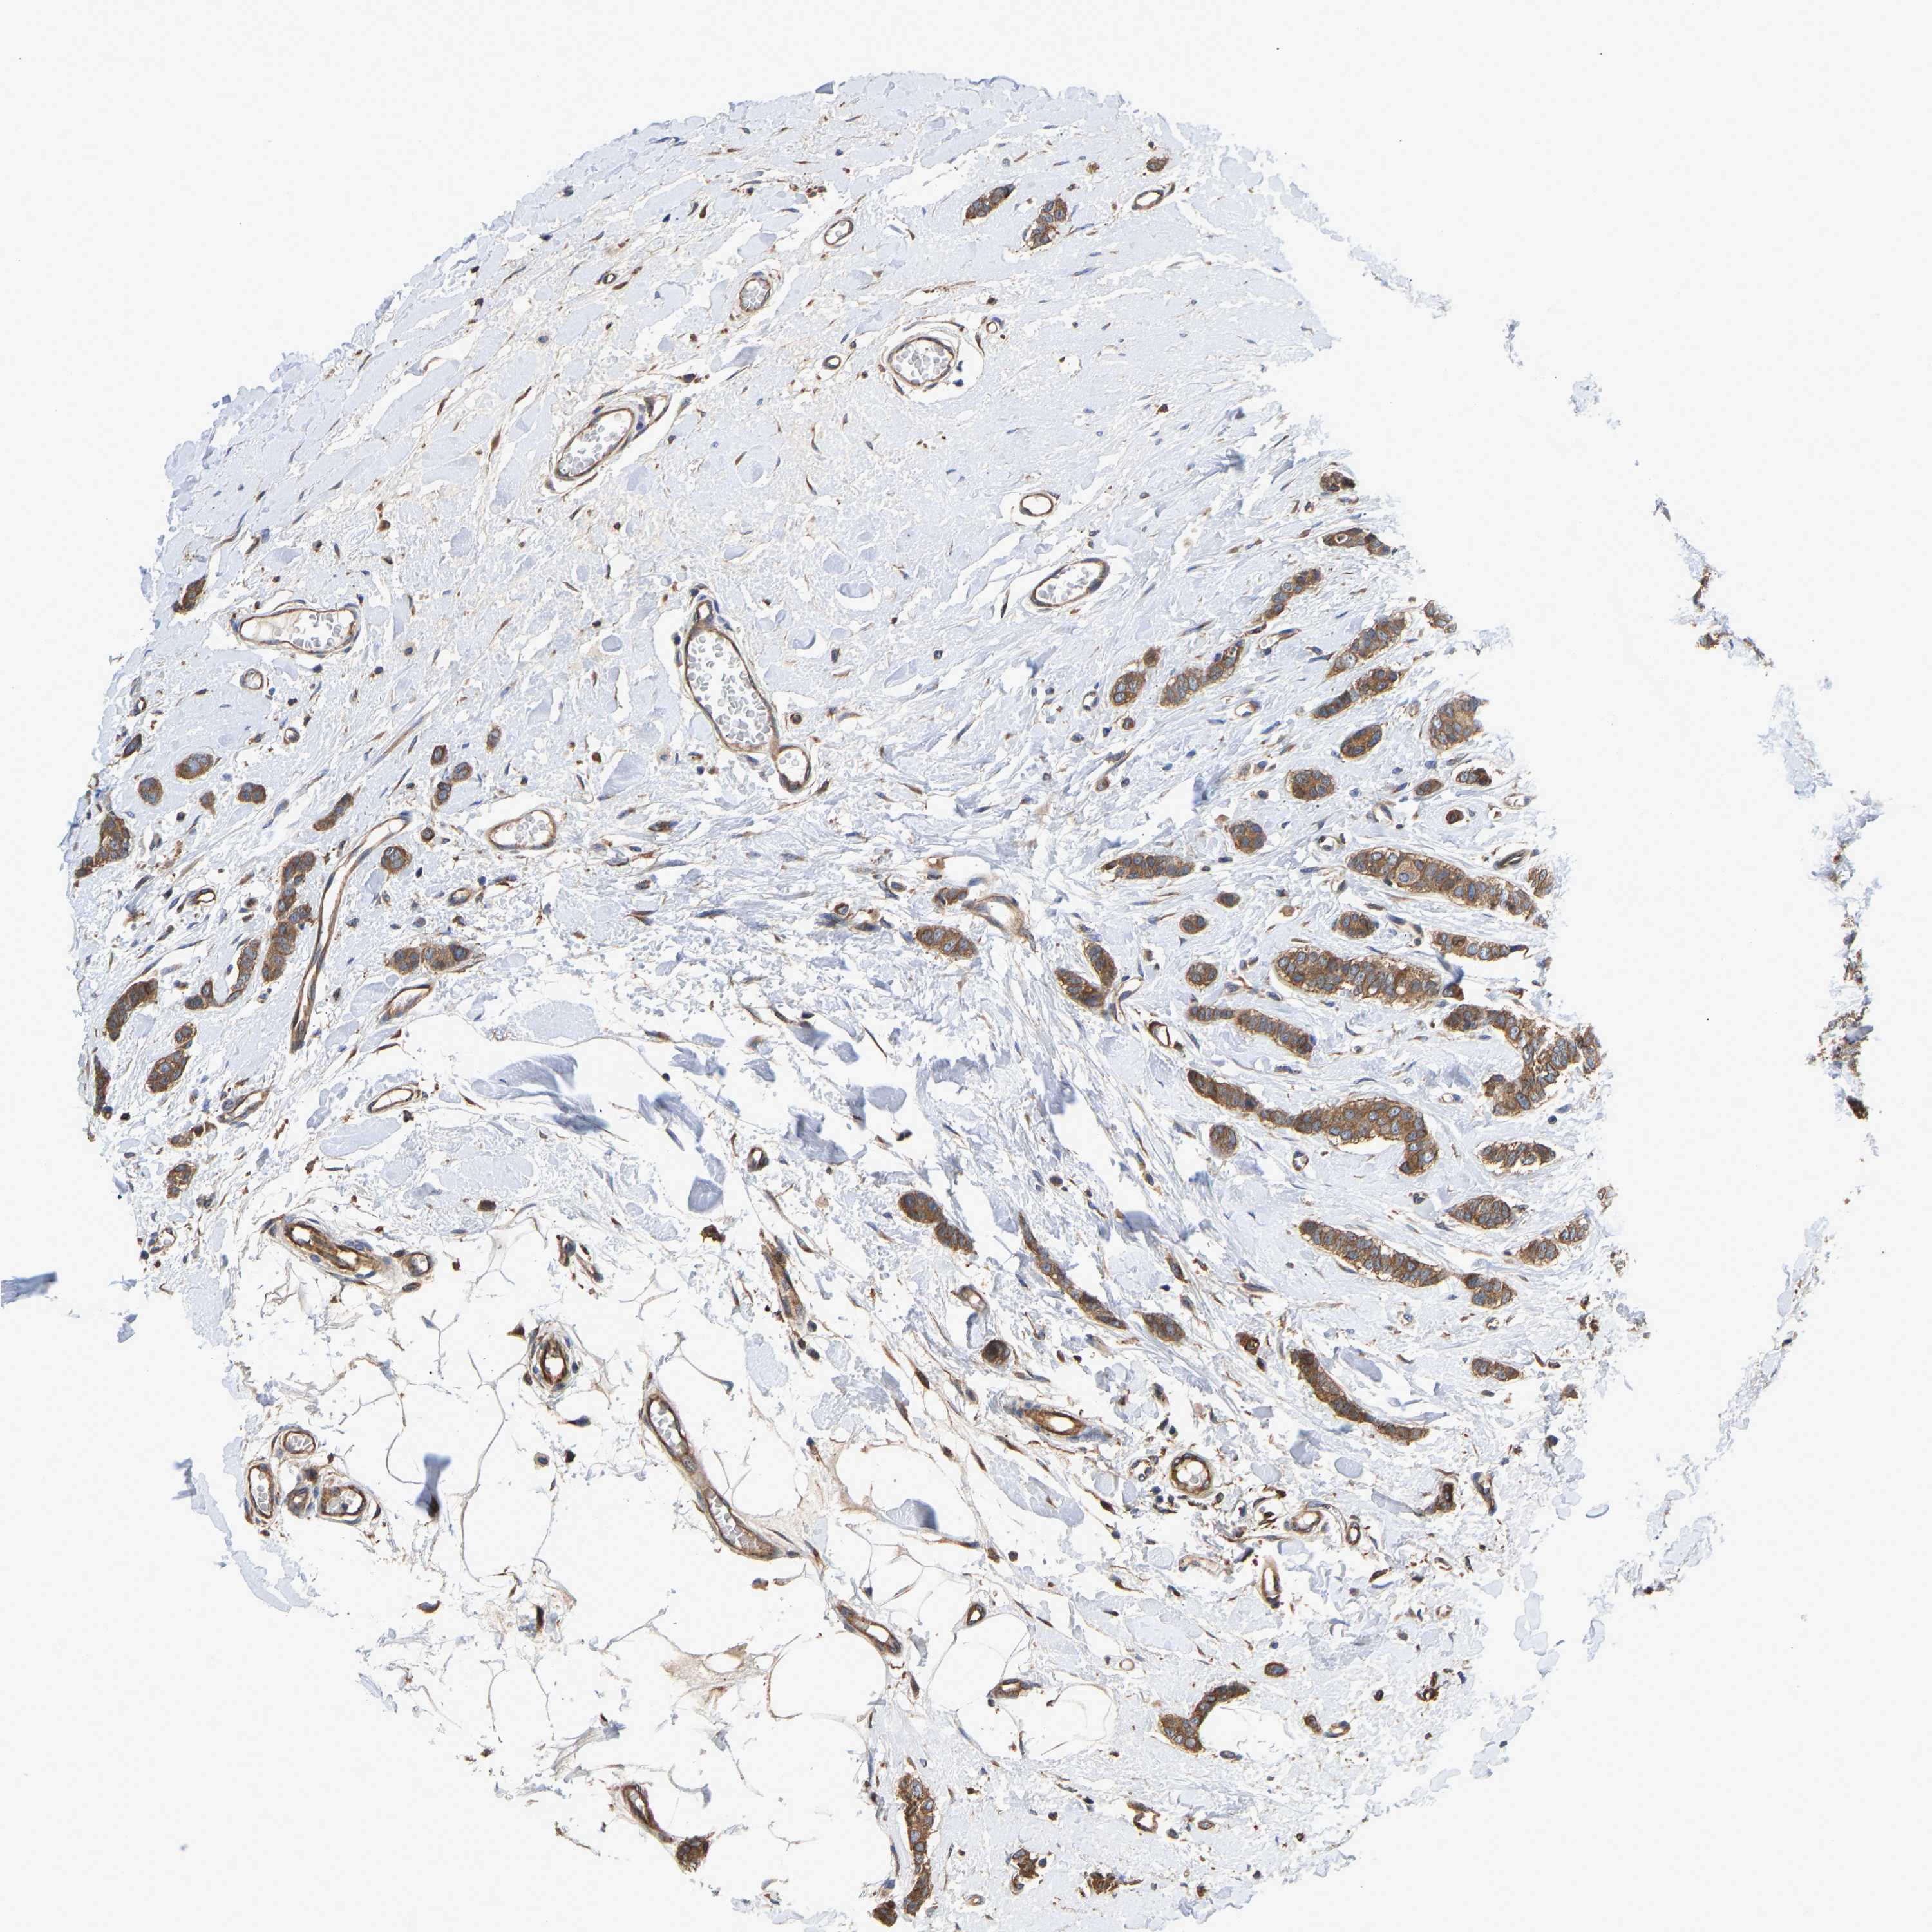

CANCER BREAST CANCER Show tissue menu

BRCA TCGA BRCA VALIDATION PROTEIN EXPRESSION

ANTIBODIES

AND

VALIDATION